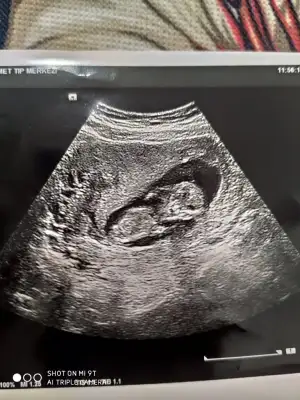

Sanki alt tarafta çıkıntı va gibi ama bileedim

Dik değil acısı poziyon değiştirmediyse kiz gibiSanki alt tarafta çıkıntı va gibi ama bileedim

Diğer taraftaki konumda yazdim erkek gibi sanki tekrar USG paylasin12 haftalık bana da bakabilir misiniz![]()

12 haftalık USG bu çok teşekkür ederimDiğer taraftaki konumda yazdim erkek gibi sanki tekrar USG paylasin

Başka USG paylaşın12 haftalık USG bu çok teşekkür ederim![]()